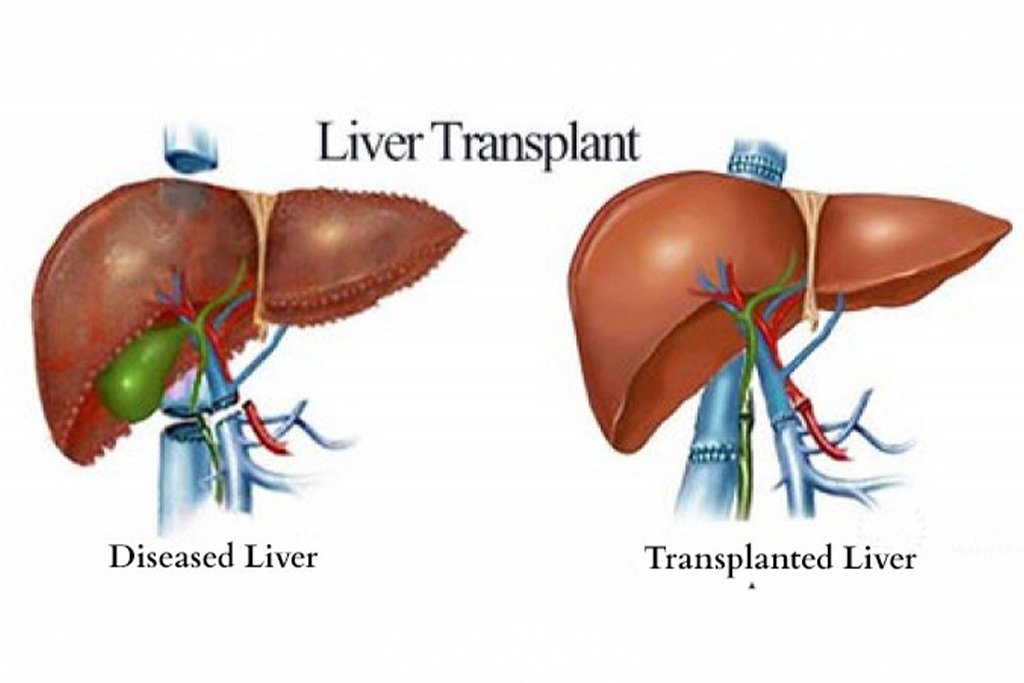

Liver transplantation is a complex surgical procedure in which a damaged or non-functioning liver is replaced with a healthy one from a donor. It is often the only viable treatment for patients facing end–stage liver disease, acute liver failure, or certain liver cancers.

A liver transplant is recommended when chronic liver disease leads to liver failure or when a patient develops liver cancer that cannot be treated with other methods.

- Cirrhosis – Scarring of the liver due to alcohol, hepatitis, or fatty liver disease

- The damaged liver is removed and replaced with the healthy donor liver

- The blood vessels and bile ducts are reconnected to ensure normal liver function